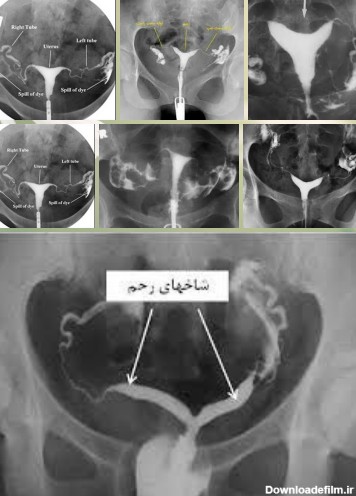

جواب عکس رنگی رحم سالم نی نی سایت

جواب عکس رنگی رحم نی نی سایت

عکس رنگی از رحم سالم

جواب عکس رنگی رحم سالم

عکس رنگی رحم سالم

عکس جواب عکس رنگی رحم

نتیجه عکس رنگی رحم نی نی سایت

جواب عکس رنگی از رحم

عکس رنگی رحم سالم نی نی سایت